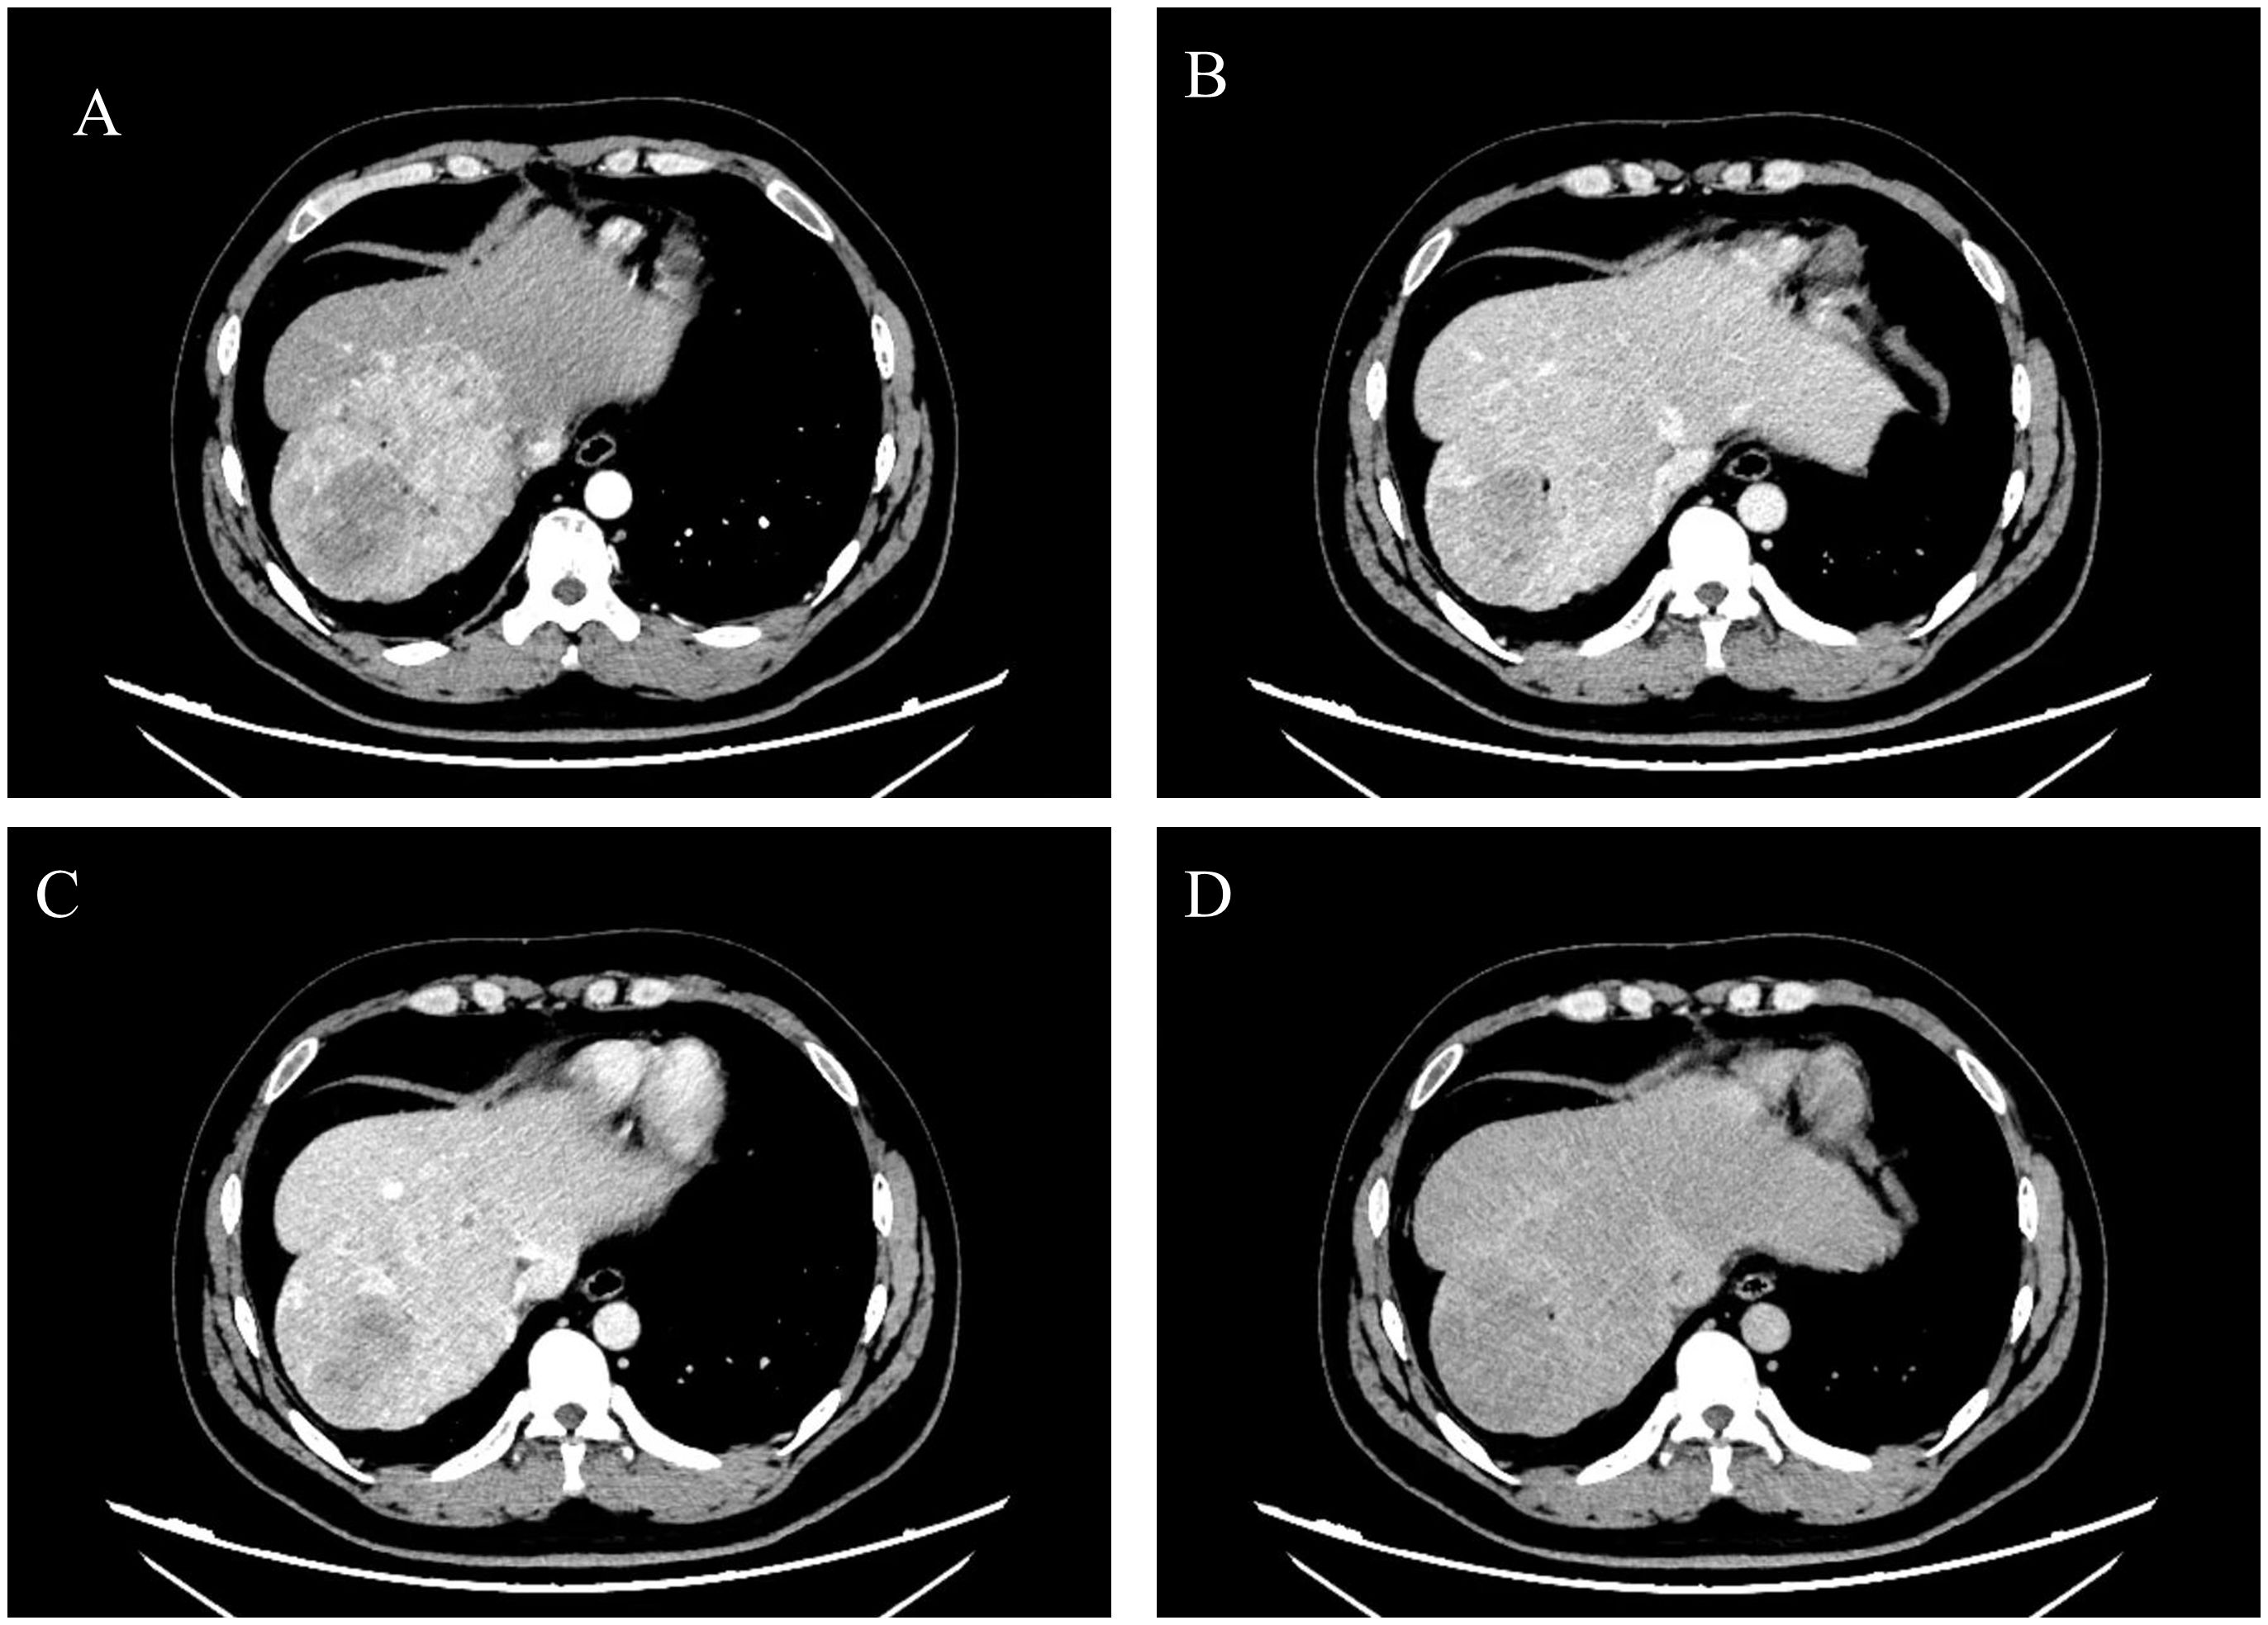

The patient recovered well postoperatively and was discharged uneventfully. However, during follow-up, it was noted that he continued to experience persistent right-sided low back pain, which progressively interfered with his daily activities, work, and sleep. A lumbar spine magnetic resonance imaging(MRI) performed in October 2024 revealed osteolytic destruction of the right 12th rib, the T11 vertebral body, and the right pedicle, accompanied by an epidural mass, malignant metastasis was considered (Figure 4A). Positron Emission Tomography-Computed Tomography (PET-CT) also showed irregular morphology of the right 12th rib, the T11 vertebral body and the right pedicle, accompanied by bone destruction, increased metabolism, considered metastasis. No other abnormalities were detected (Figures 4B, C). Then the patient received stereotactic radiotherapy for bone metastasis(BM), with the radiation dose specified as follows: 95% Planning Target Volume(PTV) 1: 45Gy in 10 fractions(4.5Gy per fraction); 95% PTV2: 40Gy in 10 fractions(4Gy per fraction), totaling 20 fractions. After the completion of radiotherapy, we performed a prophylactic transcatheter arterial chemoembolization(TACE) for the patient. During the procedure, selective hepatic angiography was conducted, and the results showed no abnormal enhancement in the liver. Subsequently, the patient received regular follow-up visits at the outpatient clinic. Both AFP testing and abdominal imaging examinations revealed no evidence of tumor recurrence. The patient’s pain symptoms resolved, and he resumed normal work and daily life.

Figure 4

MRI and PET/CT images show various cross-sectional views of the upper body. Panel A displays an MRI with a red arrow indicating a highlighted area. Panels B and C show multiple PET/CT images in axial, sagittal, and coronal views with crosshairs used for alignment.

Figure 4. MRI indicates bone destruction, suggesting bone metastasis (A); PET-CT reveals irregular morphology of the right 12th rib, 11th thoracic vertebra, and right vertebral arch, accompanied by bone destruction and increased metabolism, suggesting metastasis (B, C).